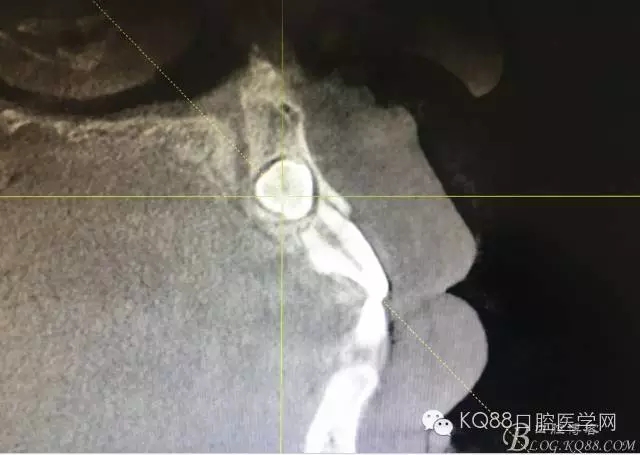

圖2. CBCT檢查:13橫位埋伏阻生、導(dǎo)致11牙根吸收約1/2.

圖3.CBCT的影像檢查資料:矢狀面13牙冠壓迫11牙根吸收約1/2,并且確定13牙冠靠近唇側(cè),手術(shù)入路定在唇側(cè)